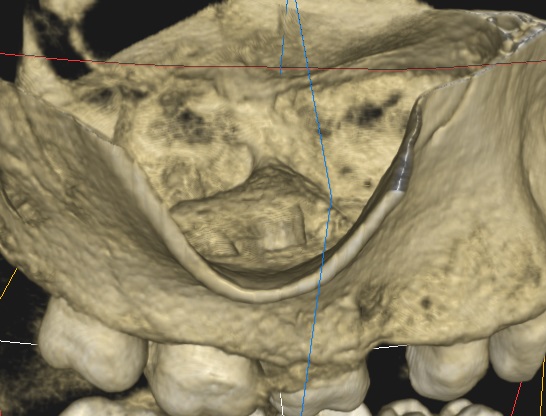

Ryc. 5. Rekonstrukcja 3D – obraz zmiany z boku.

Ryc. 6. Rekonstrukcja 3D – obraz zmiany z góry.